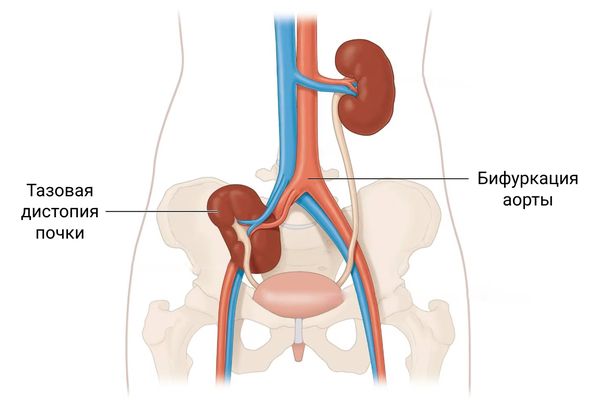

Медицинские изображения и объяснения агенезии почки

Раздел: Снимки-откровения